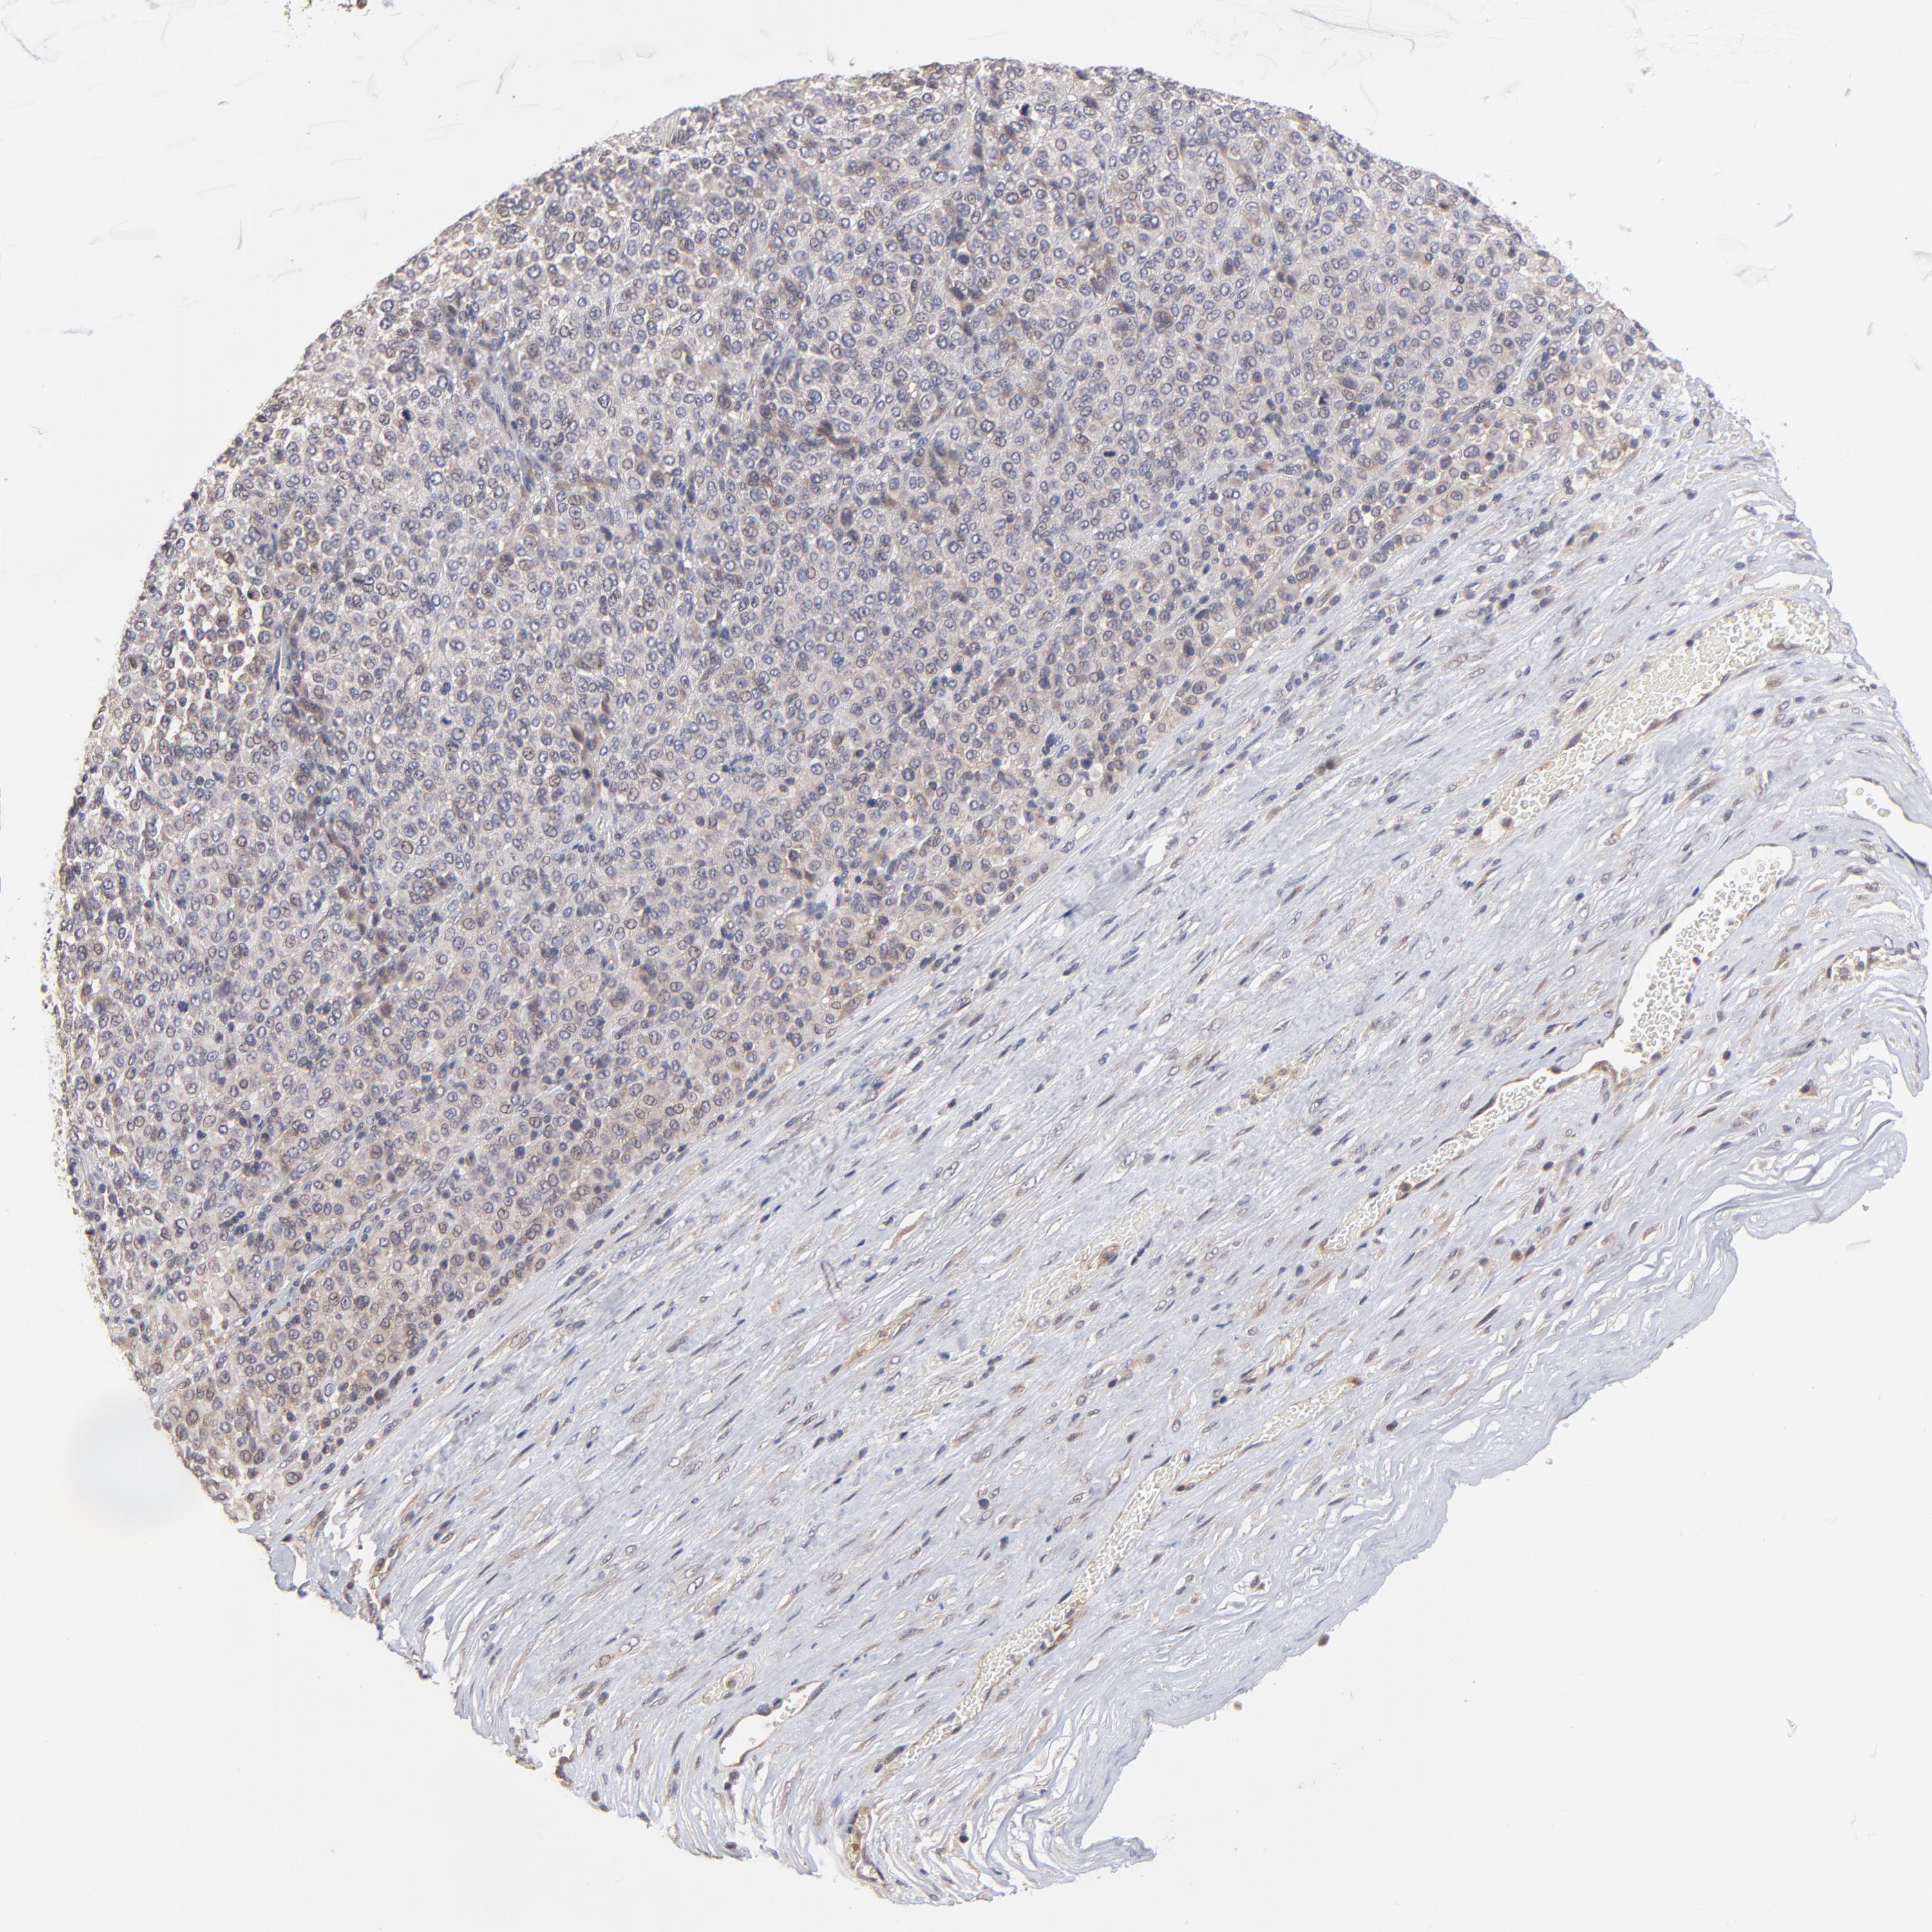

MELANOMA - Protein expressioni

A mouse-over function shows sample information and annotation data. Click on an image to view it in a full screen mode. Samples can be filtered based on level of antibody staining by selecting one or several of the following categories: high, medium, low and not detected. The assay and annotation is described here.

Note that samples used for immunohistochemistry by the Human Protein Atlas do not correspond to samples in the TCGA dataset.

Antibody stainingi

Antibody staining in the annotated cell types in the current human tissue is reported as not detected, low, medium, or high, based on conventional immunohistochemistry profiling in selected tissues. This score is based on the combination of the staining intensity and fraction of stained cells.

Each image is clickable and will lead to virtual microscopy that enables deeper exploration of all samples and also displays staining intensity scores, fraction scores and subcellular localization as well as patient and tissue information for each sample.

Antibody HPA003319

Staining

High

Medium

Low

Not detected

Intensity

Strong

Moderate

Weak

Negative

Quantity

>75%

75%-25%

<25%

None

Location

Nuclear

Cytoplasmic/membranous

Cytoplasmic/membranous,nuclear

Malignant melanoma, NOS

Malignant melanoma, Metastatic site